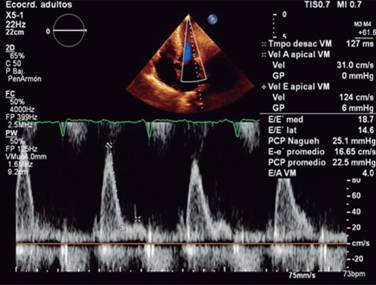

Echocardiogram is the study more commonly used in patients with a suspected or confirmed diagnosis of cardiac amyloidosis. It gives us structural and functional information about eventual amyloid heart disease. Typically shows an increased thickness of left ventricular free wall and the septum that can be misdiagnosed as hypertrophic cardiomyopathy or hypertensive cardiomyopathy.16 In its classic echocardiographic presentation it has a speckled granular pattern that was the typical echocardiographic image, but know we know this pattern is quite unspecific and may appear in many other infiltrative heart disease, an also several patients with corroborated cardiac amyloidosis do not have this previously thought characteristic granular pattern, so even if it is a useful echocardiographic sign, we cannot rely on it for the diagnosis of cardiac amyloidosis. Other echo findings include increase thickness of atrioventricular valves, interatrial septum and free wall of right ventricle. Tissue Doppler e’ septal is low and E/e’ ratio is high, an indication of a high filling pressure of left ventricle (Figure 2). Left ventricular ejection fraction might be normal or minimally diminished, and a characteristic echo finding in cardiac amyloidosis is a diminished left ventricle longitudinal strain rate specifically in basal segments with preserved normal deformity in apical segments (Figures 3 and 4), there is a strain rate gradient from abnormal to normal from basal to apical segments.17,18

Figure 2: Echocardiogram: thick left ventricular wall with normal sized cavities. Enlarged atriums. Restrictive left ventricular filling as marker of increased filling pressure.